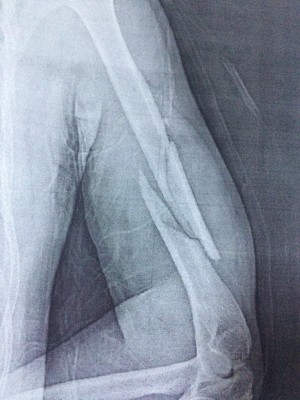

Probleme cu nervul radial